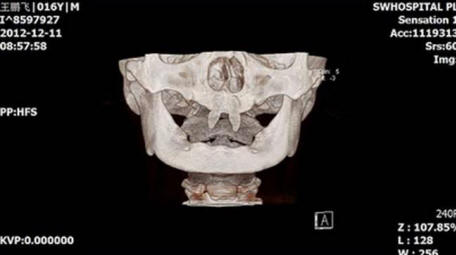

3. Teini-ikäinen on kasvanut omat vampyyrihampaat

Kiinalainen poika kasvatti kahta erittäin terävää etuhammasta saaden hänet näyttämään vampyrilta. Joulukuussa 2012 äiti nimeltä Wang Hui vei poikansa Wang Penfein paikalliselle sairaala tutkittavaksi. Chongqing Municipal Boy After syntymä on erittäin huonosti kasvavaa, ja hänen suussaan ilmestyi kaksi terävää keila.

Wang Hui yritti selvittää syyn näiden pojan ilmestymiseen epänormaalit muodostelmat ja vieraili lukemattomissa lääkäreitä, mutta se ei tuottanut suurta menestystä. Lääkärit alkaen Southwestern Hospital sairaalan mukaan hänen poikansa voidaan tehdä leikkaus vasta kun hänestä tulee aikuinen.

valokuva avoimista lähteistä

Tämän toimenpiteen kustannukset voivat vaihdella 70 000 – 80 000 RMB, se on noin 15 000 dollaria. Wang Huin mukaan hänen poikastaan on tulossa yhä enemmän vetäytyy ja taistelee usein luokkatovereiden kanssa, kuka kuiskaa häntä tai katsoa kysyntää hänelle.